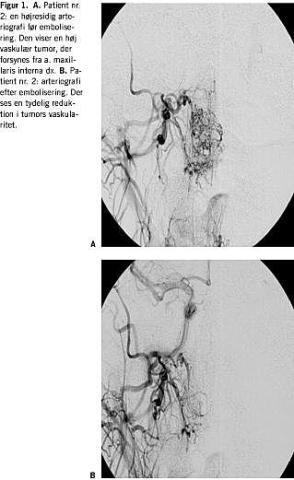

Partiklerne blandes i saltvand og røntgenkontrast. Der emboliseres, indtil flow i tumoren er ophørt. Hvis der herefter fortsat persisterer store proksimale kar uden sidegrene, injiceres der histoacryl/lipiodol i forholdet 1:4 eller 1:5. Dette lukker de store kar og muliggør resektion helt ind til knoglen uden blødning. Det er kun muligt at embolisere grene fra a. carotis externa. Eventuel forsyning direkte fra carotis interna eller fra a. etmoidalis, som afgår fra a. opthalmica, kan ikke emboliseres på grund af risikoen for intrakranielle embolier. Oftest kan tumorperfusionen dog reduceres med 90-95%, når forsyningen fra a. carotis externa er emboliseret (Figur 1A og 1B ).

Gennemsnitsalderen og gennemsnitstiden fra debutsymptom til diagnose i vores materiale er i overensstemmelse med, hvad der er beskrevet i litteraturen (Tabel 1 ). Hos vores patienter anvendte vi præoperativ partikelembolisering i forbindelse med 13 ud af 14 operationer. I alle tilfælde var det a. maxillaris interna, der blev emboliseret, da tumors hovedforsyning i alle tilfælde kom fra denne arterie. Patient nr. to havde bilateral forsyning af tumoren fra a. maxillaris interna både ved primær embolisering og ved recidivtumor. Man måtte denne ene gang afstå fra at embolisere i højre side på grund af en shunt gennem tumoren til forsyningen fra a. carotis interna. Samme patient havde ved recidiv forsyning fra truncus menigohyperphysialis, som er en sidegren fra carotis interna og derfor ikke kunne emboliseres. Det drejede sig i begge tilfælde kun om en mindre forsyning til tumoren. Patient nr. otte havde også bilateral forsyning fra både a. maxillaris interna og a. pharyngea acendens, som alle blev emboliseret. I de resterende tilfælde var forsyningen unilateral. I et tilfælde (patient nr. fire ved recidiv) undlod man embolisering, da tumor var meget lille. Ved patient nr. tre afstod man fra at embolisere en mindre gren fra a. temporalis, da man i så fald skulle lukke hele a. temporalis, hvilket kunne give hudnekroser.